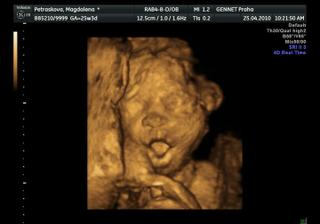

25.4.2010-razíme na 4D utz tak snad se nám princezna ukáže v plné kráse =0*

no vypadaj fakt velký =D